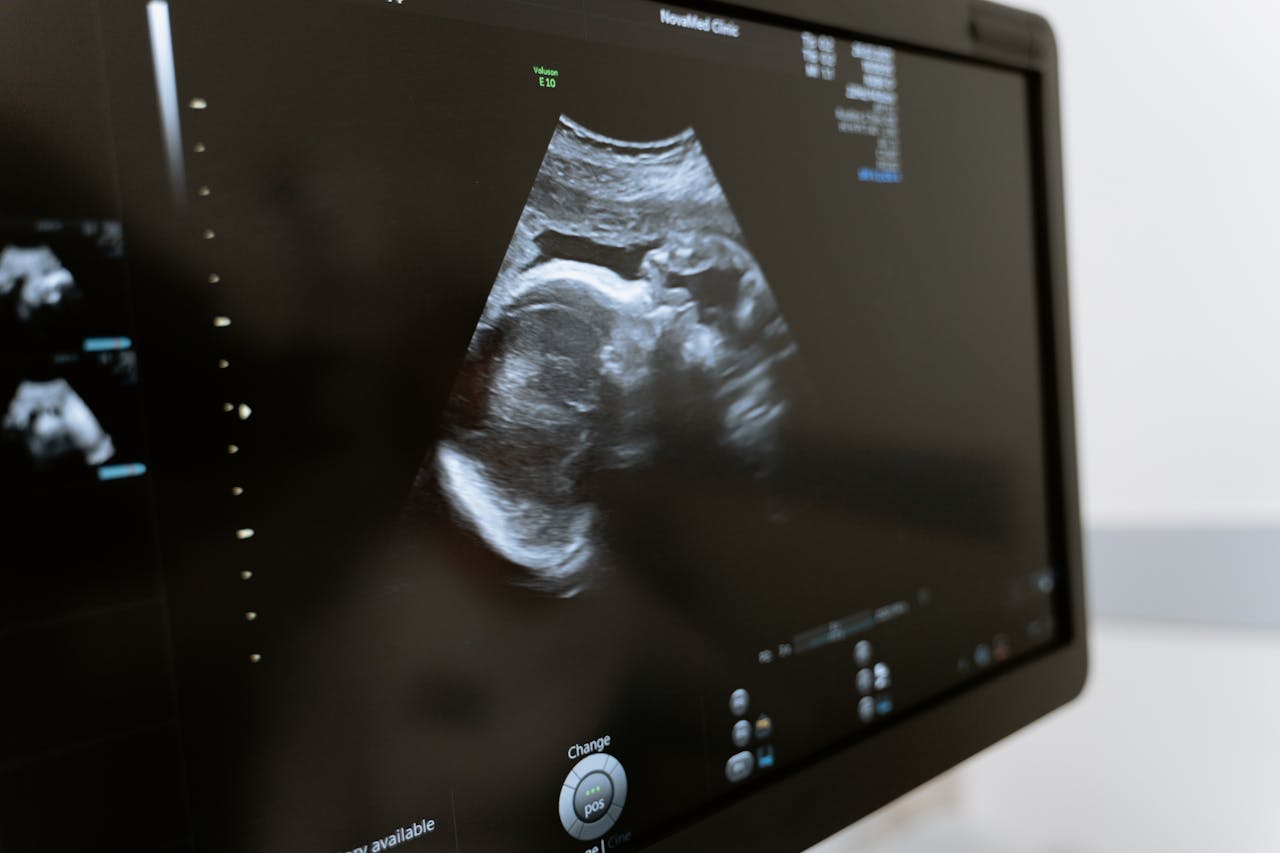

Oferuję kompleksowe usługi ginekologiczne z indywidualnym podejściem do każdej pacjentki. Zaufaj mojemu doświadczeniu i wiedzy.